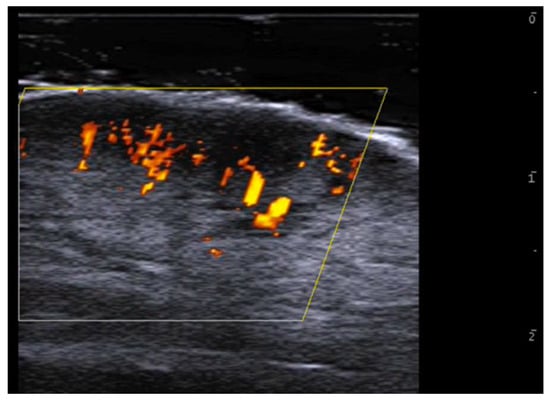

- Cataldo-Cerda, K.; Wortsman, X. Dissecting Cellulitis of the Scalp Early Diagnosed by Color Doppler Ultrasound. Int. J. Trichology 2017, 9, 147–148. [Google Scholar] [CrossRef]